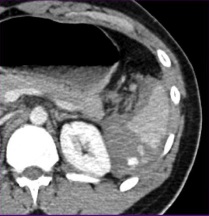

脾创伤的CT特征和非手术治疗的失败率增加有关,决定这类病人是否需要紧急的血管造影或栓塞,甚至是外科手术【3】。其中最重要的两条是活动性出血的象征,造影剂外溢和脾血管损伤的证据如假性动脉瘤、损伤后动静脉瘘。 造影剂外溢 造影剂外溢的表现:不规则和线样造影剂外溢出现在脾实质或包膜下间隙。

脾血管损伤:假性动脉瘤,外伤后动静脉瘘。在动脉期很难和活动性出血鉴别,但延时期会消失(wash-out)。